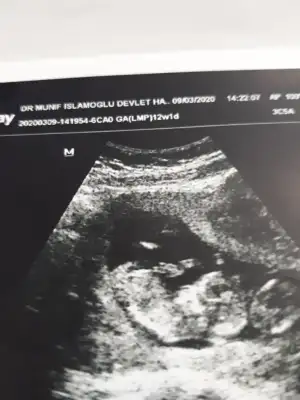

Erkek gibiTahmin edebilcek olan var mı lütfen dr söyledi 12. Haftada bakalım aynı mı

Net miErkek gibi

16 degil 11 -12 yada 13 haftalar olmalı dr söylemedimi sanki erkek gibi ama dediğim haftalara tahmin ediyorum